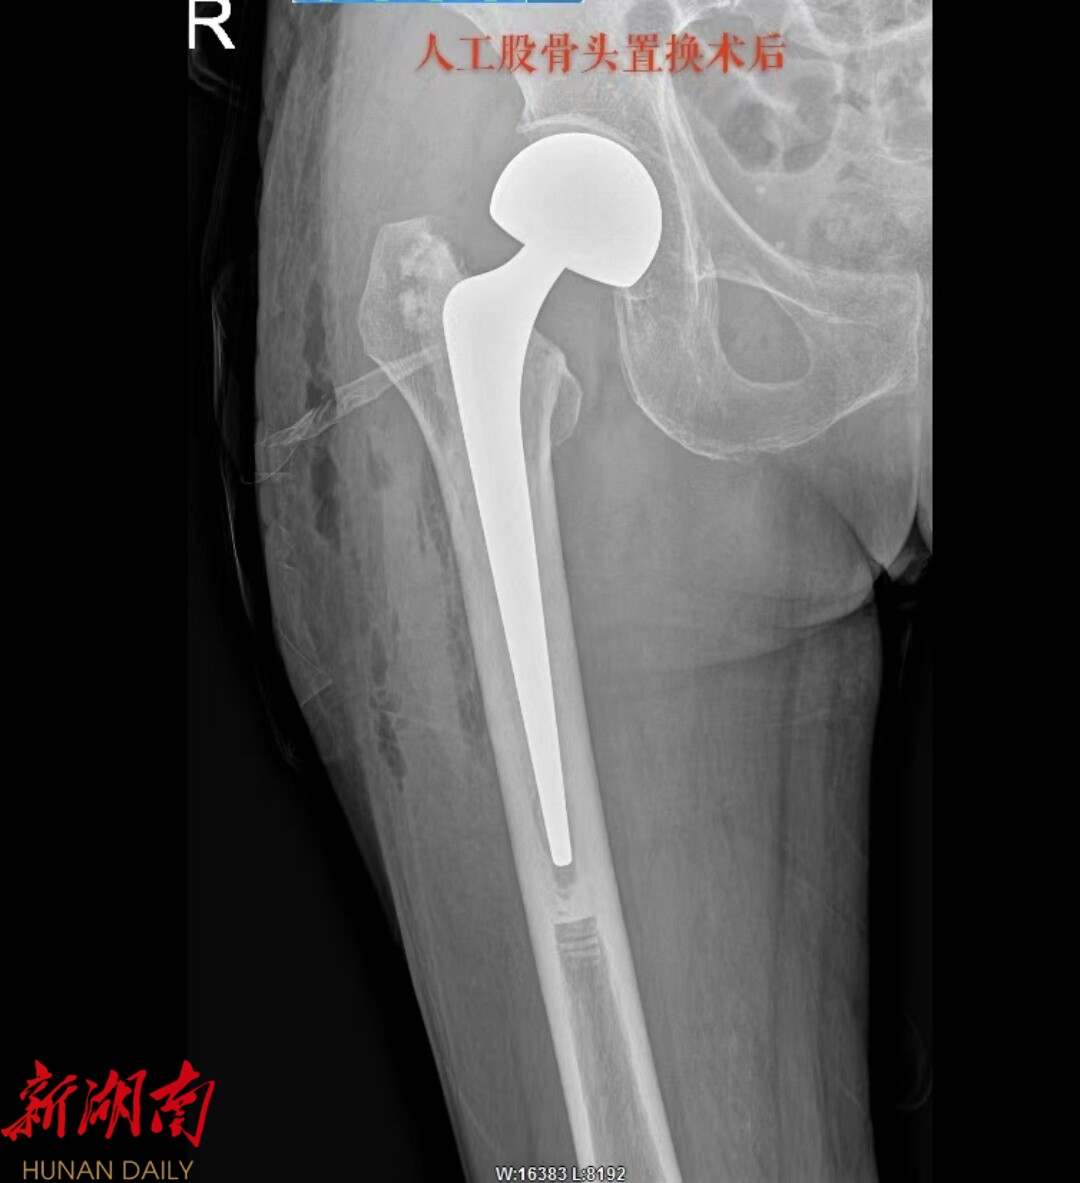

81 岁患者的朱奶奶,因摔伤致右髋部疼痛 2 天入院,确诊为右侧股骨颈骨折。永兴县人民医院骨二科团队在充分评估朱奶奶的病情后,决定采用 “保留梨状肌人工股骨头置换术”,术后第一天,朱奶奶便在医护人员的保护下顺利下地站立并行走,疼痛感明显减轻,关节活动功能恢复良好。

永兴县人民医院骨二科团队率先引进并成熟开展多例 “保留梨状肌的人工股骨头置换术”,采用改良后外侧小切口入路。在医生最熟悉的后外侧入路基础上进行改良。通过采用更小的切口(约5-8cm)和更精细的软组织分离技术,在不切断梨状肌及其附着点的前提下,借助人体自然的肌肉间隙——梨状肌和臀小肌之间的缝隙进入关节,巧妙地暴露手术视野,显露髋关节囊,精准植入假体,完整保留髋关节的后方稳定结构。